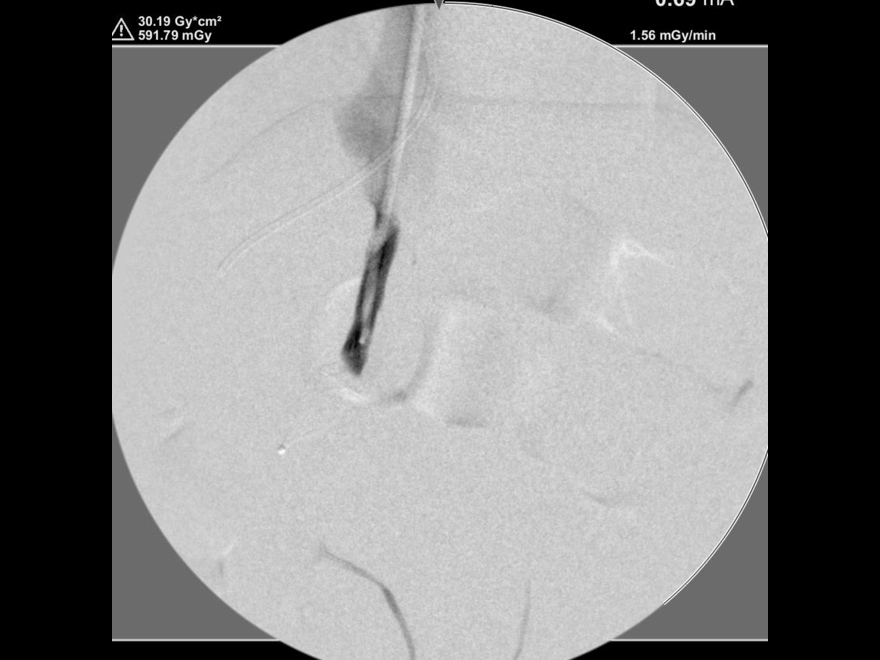

プラグ塞栓後の造影検査